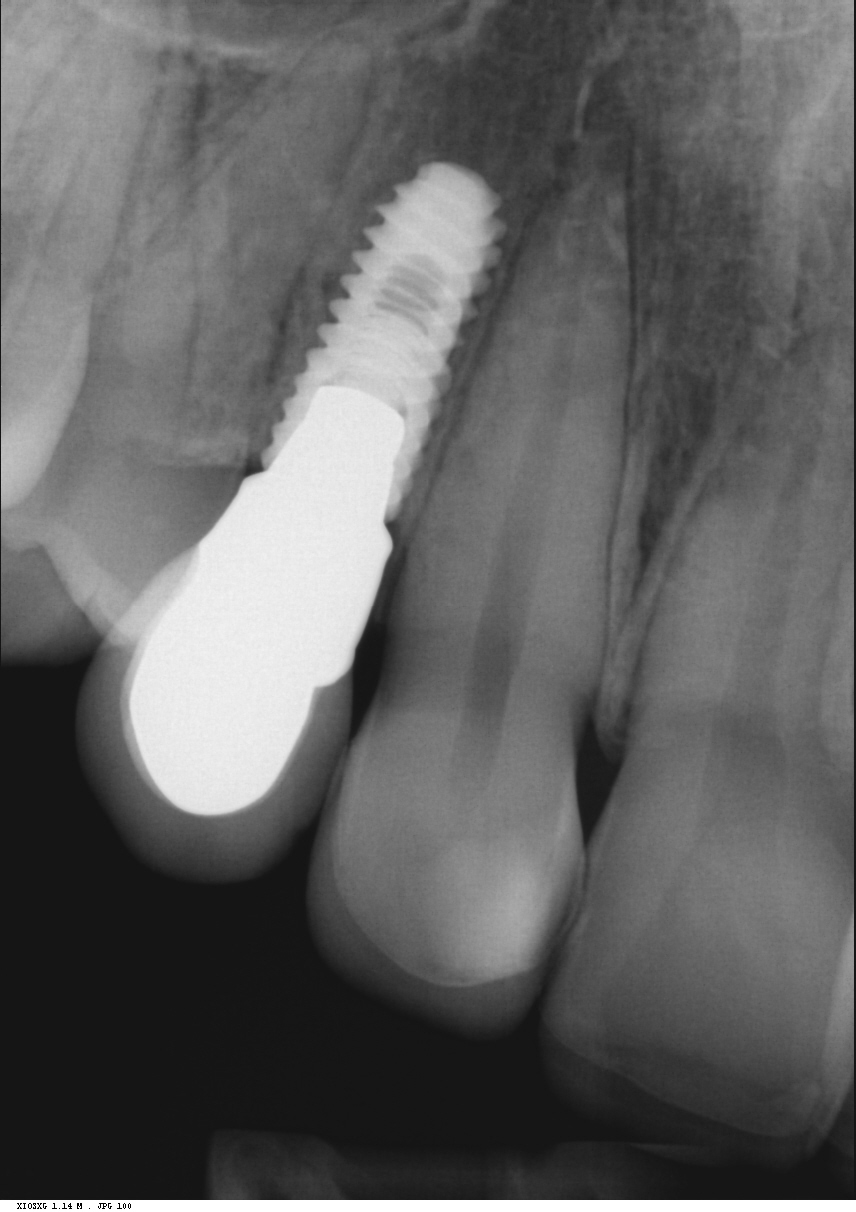

Implantit paikoillaan 1/3

Implantit paikoillaan 2/3

Implantit paikoillaan 3/3

Radiologinen näkymä lopputilanteesta. Implanttikruunut paikoillaan.

Sama tilanne toiselta puolelta